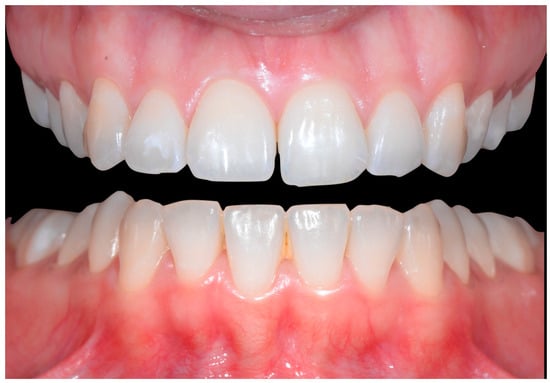

A 26-year-old female patient was referred by her general dentist for suspected wire syndrome. Orthodontic treatment had been performed 10 years previously, and bonded restorations had been fitted at the end of the treatment. The patient mentioned several episodes of breakage/adhesion, without further details. She has good oral hygiene and a right and left Class I (Figure 5).

Figure 5.

Intermediate wire syndrome. Frontal and lateral views.

In Figure 6, 11 and 21 show a difference in incisal edge height and gingival margin. Tooth 41 shows gingival recession to the muco-gingival junction (Cairo’s RT1) with root visibility. Tooth 33 had a significant lingual tilt (coronal–lingual torque), not symmetrical to tooth 43.

Figure 6.

Intermediate wire syndrome. Frontal view.

The root of tooth 21 is visible through the gingiva (Figure 7). Figure 8 shows the extent of gingival recession on tooth 41.

The occlusal views provide additional relevant information (Figure 9 and Figure 10). A maxillary retainer was present on 11 and 21 only and a difference in visibility of the vestibular surfaces (differential torque) on these same teeth was noted.

Figure 9.

Intermediate wire syndrome. Occlusal view.

Figure 10.

In the mandible, the retainer was broken distal to 42 and, despite being intact on 33, this tooth had increased visibility of its vestibular surface compared to its contralateral tooth (differential torque). Finally, teeth 31 and 41 also showed a difference in the visibility of their vestibular surfaces (differential torque). Ultimately, the patient was diagnosed with an X-effect wire syndrome on 21, an X-effect wire syndrome on 41, and a Twist-effect wire syndrome on 33.